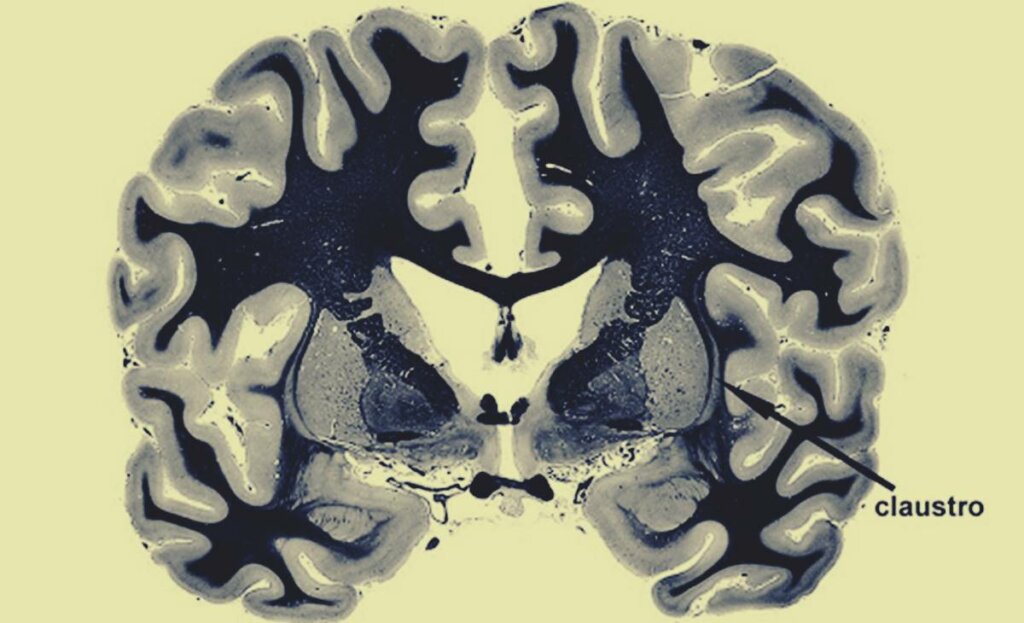

El claustro cerebral está justo debajo del neocórtex, una sustancia gris conformada por axones neuronales que nos permite procesar la información. Como sucede en múltiples estructuras cerebrales, el claustro es doble, es decir, hay uno por cada hemisferio y ambos se localizan justo a la altura de los oídos. Toda esta región está rodeada además por la sustancia blanca.